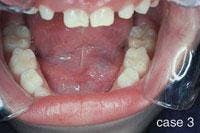

CASE 3

Ranula

1. Where is the ranula likely to occur?

a. lips

b. floor of mouth

c. labial mucosa

d. hard palate

2. What salivary gland(s) are involved in the formation of the ranula?

a. sublingual gland

b. submandibular gland

c. minor salivary glands

d. any of the above

3. What is the preferred treatment for the ranula?

a. no treatment required

b. marsupialization

c. radiation therapy

d. none of the above